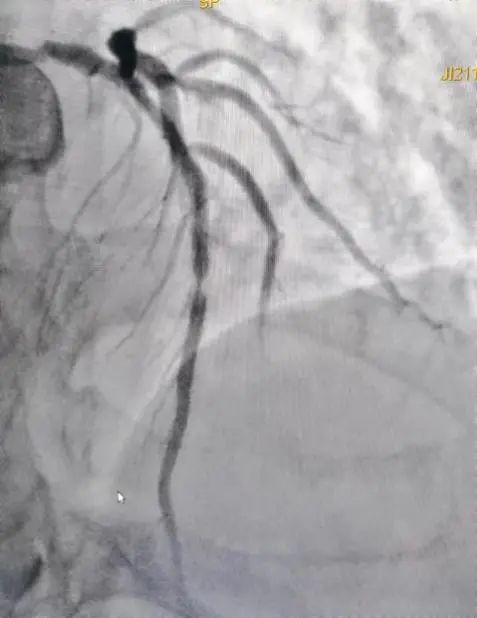

1.支架内再狭窄首选药物球囊

支架内再狭窄是指植入的冠脉支架内或支架两端5毫米节段内,由于血管内皮损伤、内皮功能失调以及新生内膜增殖等原因,导致血管管腔狭窄程度再次超过50%的疾病。由于已经放过支架并且发生了再狭窄,再放支架对于病变来讲并不理想,这时就可以选择药物球囊,通过血管内超声(IVUS)我们可以看到支架内发生了再狭窄,管腔面积不足以维持心脏的供血,患者可能会出现胸闷等症状。

这时我们可以先通过切割球囊来预处理,把支架内的斑块切开,在选择适合的药物球囊贴到病变位置,通常药物球囊要贴45秒以上,它可以把狭窄的血管扩张,并且把药物留在血管壁上。术后造影和ivus都可以看到血管管腔明显改善,达到治疗目的。